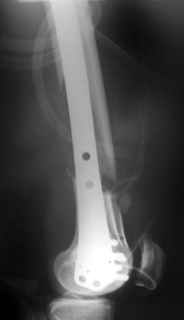

Date: 10/31/2004, 12:13 From Zsolt Balogh @ http://weborto.net/ Dear Alex, This is what we have done... As generally true for LISS look at the bone

not the hardware. There are two more screws above. The one not completely

in got damaged head. Zsolt